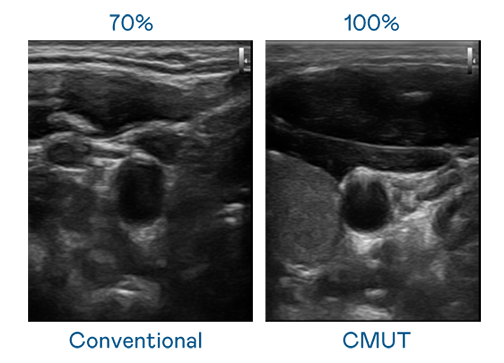

CMUT 技术是一种用电容式微机电元件来产生超音波讯号的技术。与传统 PZT 压电式技术相比,CMUT 频宽增加 30%,更宽频的超音波讯号让影像解析度大幅提升,是实现高影像品质医疗超音波扫描、促进精准医疗发展的关键技术。

大频宽带来超清晰影像

超音波影像的解析度高低,首先取决于探头能发出的讯号频宽。long8-龙8(龙八国际)唯一官方网站 CMUT 可提供高清晰的超音波讯号,提供高频宽、高灵敏度、影像纹理细节更高的超音波影像,协助医护人员缩短影像判读时间及利用精准的医疗影像进行诊断。